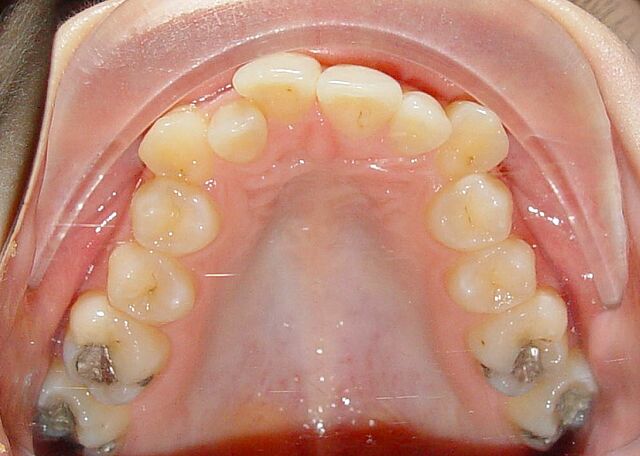

Bianca hatte eine Protrusion, einen Engstand und einen Eckzahn Hochstand. Sie wurde mit Invisalign in 24 Monaten behandelt.

• Engstand

• Protrusion